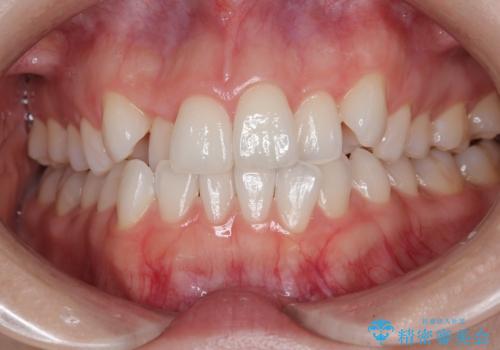

【インビザラインとワイヤー矯正】がたつきと噛み合わせを改善!